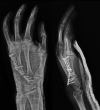

Multifocal chondrosarcoma of the hand: Case report and review of the literature

Few multifocal hand chondrosarcomas have been reported. To our knowledge, this report is the first to describe multifocal hand chondrosarcoma in a patient with no evidence of prior enchondroma, Ollier's disease, or Maffucci syndrome.